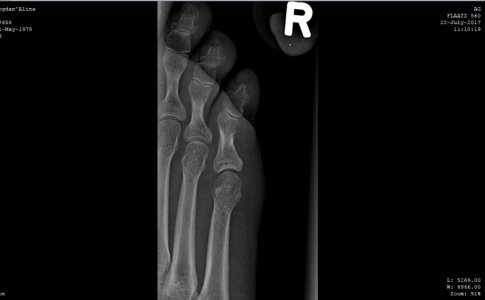

Здравствуйте! Прошу помощи. Прошло 18 дней со дня перелома мизинца (4 июля), к сожалению,находясь заграницей так и не удалось попасть к нормальному врачу, ходила с примотанным пластырем к соседнему пальцу, синяк почти прошел, сегодня сделали снимки - по -моему разницы никакой, угол отломка не изменился, при опоре на мизинец чувствуется давление и распирание внутри, будто эта кость торчит там внутри что-ли, как мешает что-то, при опоре отъезжает и смотрит немного в сторону, расстояние с соседним пальцем больше, чем на здоровой ноге. Думаю насчет возврата на родину и лечения в Москве. Вопрос - можно и нужно ли его еще как-то вправить, какой предельный срок? Не станет ли хуже от этих правок?

Забыть и ходить как есть? Какие последствия если не так срастется? Дискомфорт при ходьбе будет? Для меня это очень важно, заранее благодарю за ответ. Первый снимок - сразу после перелома 4 июля, остальные - 22 июля.